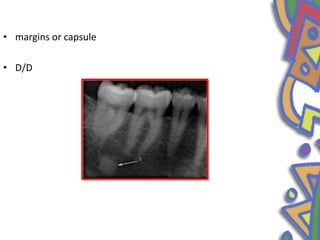

• margins or capsule

• D/D

• Mandible • Premolarmolar area • Radiographic image- radiopaque • Asymptomatic • Etiology – no

• 49.

• margins orcapsule • D/D